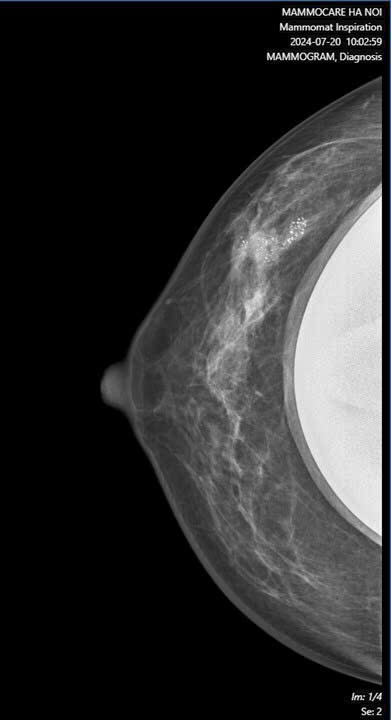

Cụ thể, kết quả X-quang cho thấy vú phải của chị có một khối nhân giảm âm với bờ tua gai trục dọc, bên trong có vôi hóa nhỏ với kích thước khoảng 12x13mm, cùng với một hạch nách phải có kích thước khoảng 13x16mm. Do kết quả nghi ngờ, chị P đã được chỉ định làm sinh thiết kim lõi và kết quả chẩn đoán là ung thư biểu mô xâm nhập, NOS, độ II, và di căn hạch nách.

Đáng chú ý, 6 tháng trước, khi chị P tiến hành đặt túi ngực, chỉ có siêu âm được thực hiện để kiểm tra. Tổn thương vi vôi hóa chỉ được phát hiện khi thực hiện chụp X-quang vú. Mặc dù tình trạng túi ngực không có gì bất thường, nhưng phát hiện ung thư vú khi được chụp X-quang đã khiến việc điều trị trở nên cần thiết và cấp bách. Hiện tại, chị P đã nhập viện K để bắt đầu điều trị ung thư.

Điều đáng nói là, khi chị P thực hiện phẫu thuật đặt túi ngực cách đây 6 tháng, chỉ có siêu âm được thực hiện để kiểm tra. Tuy nhiên, tổn thương vi vôi hóa chỉ được phát hiện khi thực hiện chụp X-quang vú. Tổn thương ung thư vú không thể được phát hiện chỉ qua siêu âm mà cần phải kết hợp với các phương pháp chẩn đoán hình ảnh khác, như X-quang vú.